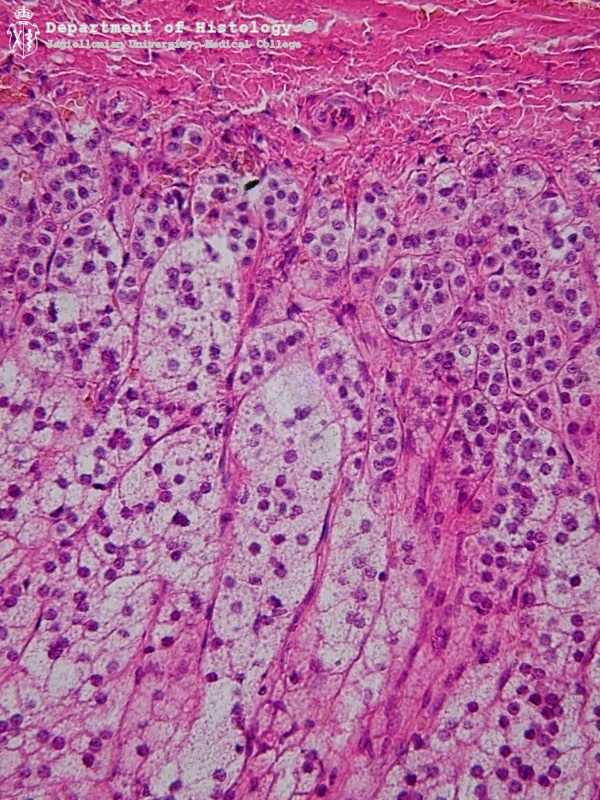

6. Warstwa kłębkowata i pasmowata kory nadnerczy

Zona glomerulosa and zona fasciculata of the adrenal cortex